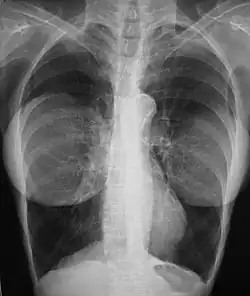

The presence of radiologically opaque breast implants (either saline or silicone) might interfere with the radiographic sensitivity of the mammograph, that is, the image might not show any tumor(s) present. In this case, an Eklund view mammogram is required to ascertain either the presence or the absence of a cancerous tumor, wherein the breast implant is manually displaced against the chest wall and the breast is pulled forward, so that the mammograph can visualize a greater volume of the internal tissues; nonetheless, approximately one-third of the breast tissue remains inadequately visualized, resulting in an increased incidence of mammograms with false-negative results.[119][120]

The breast cancer studies Cancer in the Augmented Breast: Diagnosis and Prognosis (1993) and Breast Cancer after Augmentation Mammoplasty (2001) of women with breast implant prostheses reported no significant differences in disease-stage at the time of the diagnosis of cancer; prognoses are similar in both groups of women, with augmented patients at a lower risk for subsequent cancer recurrence or death.[121][122] Conversely, the use of implants for breast reconstruction after breast cancer mastectomy appears to have no negative effect upon the incidence of cancer-related death.[123] That patients with breast implants are more often diagnosed with palpable—but not larger—tumors indicates that equal-sized tumors might be more readily palpated in augmented patients, which might compensate for the impaired mammogram images.[124] The ready palpability of the breast-cancer tumor(s) is consequent to breast tissue thinning by compression, innately in smaller breasts a priori (because they have lesser tissue volumes), and that the implant serves as a radio-opaque base against which a cancerous tumor can be differentiated.[125]

The breast implant has no clinical bearing upon lumpectomy breast-conservation surgery for women who developed breast cancer after the implantation procedure, nor does the breast implant interfere with external beam radiation treatments (XRT); moreover, the post-treatment incidence of breast-tissue fibrosis is common, and thus a consequent increased rate of capsular contracture.[126] There is tentative evidence that women who have had breast augmentation, have worse breast cancer prognosis.[127] The use of implants for breast reconstruction after breast cancer mastectomy appears to have no negative effect upon cancer-related death.[123][128]

There have been multiple reported cases of other adverse effects of mammography of women with breast implants; ruptures resulting from pressure exerted on the breast implant make up a majority of these cases.[129] Compression may also lead to pain or exacerbate already existing pain in the breasts.[129]